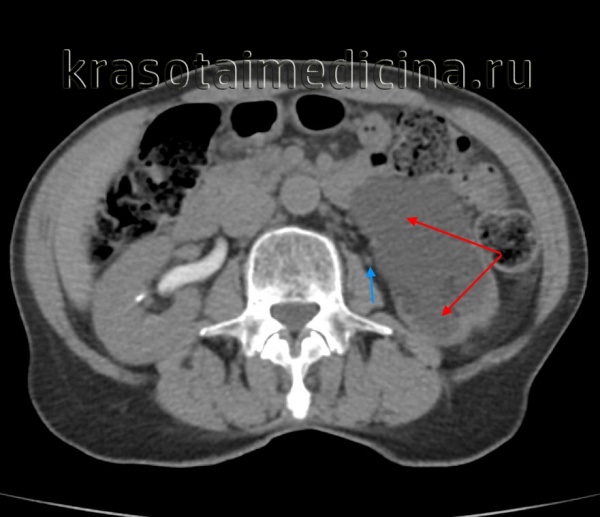

КТ-урография. Резкое расширение чашечек и лоханки левой почки (красная стрелка), отсутствие контрастирования суженного левого мочеточника (синяя стрелка).